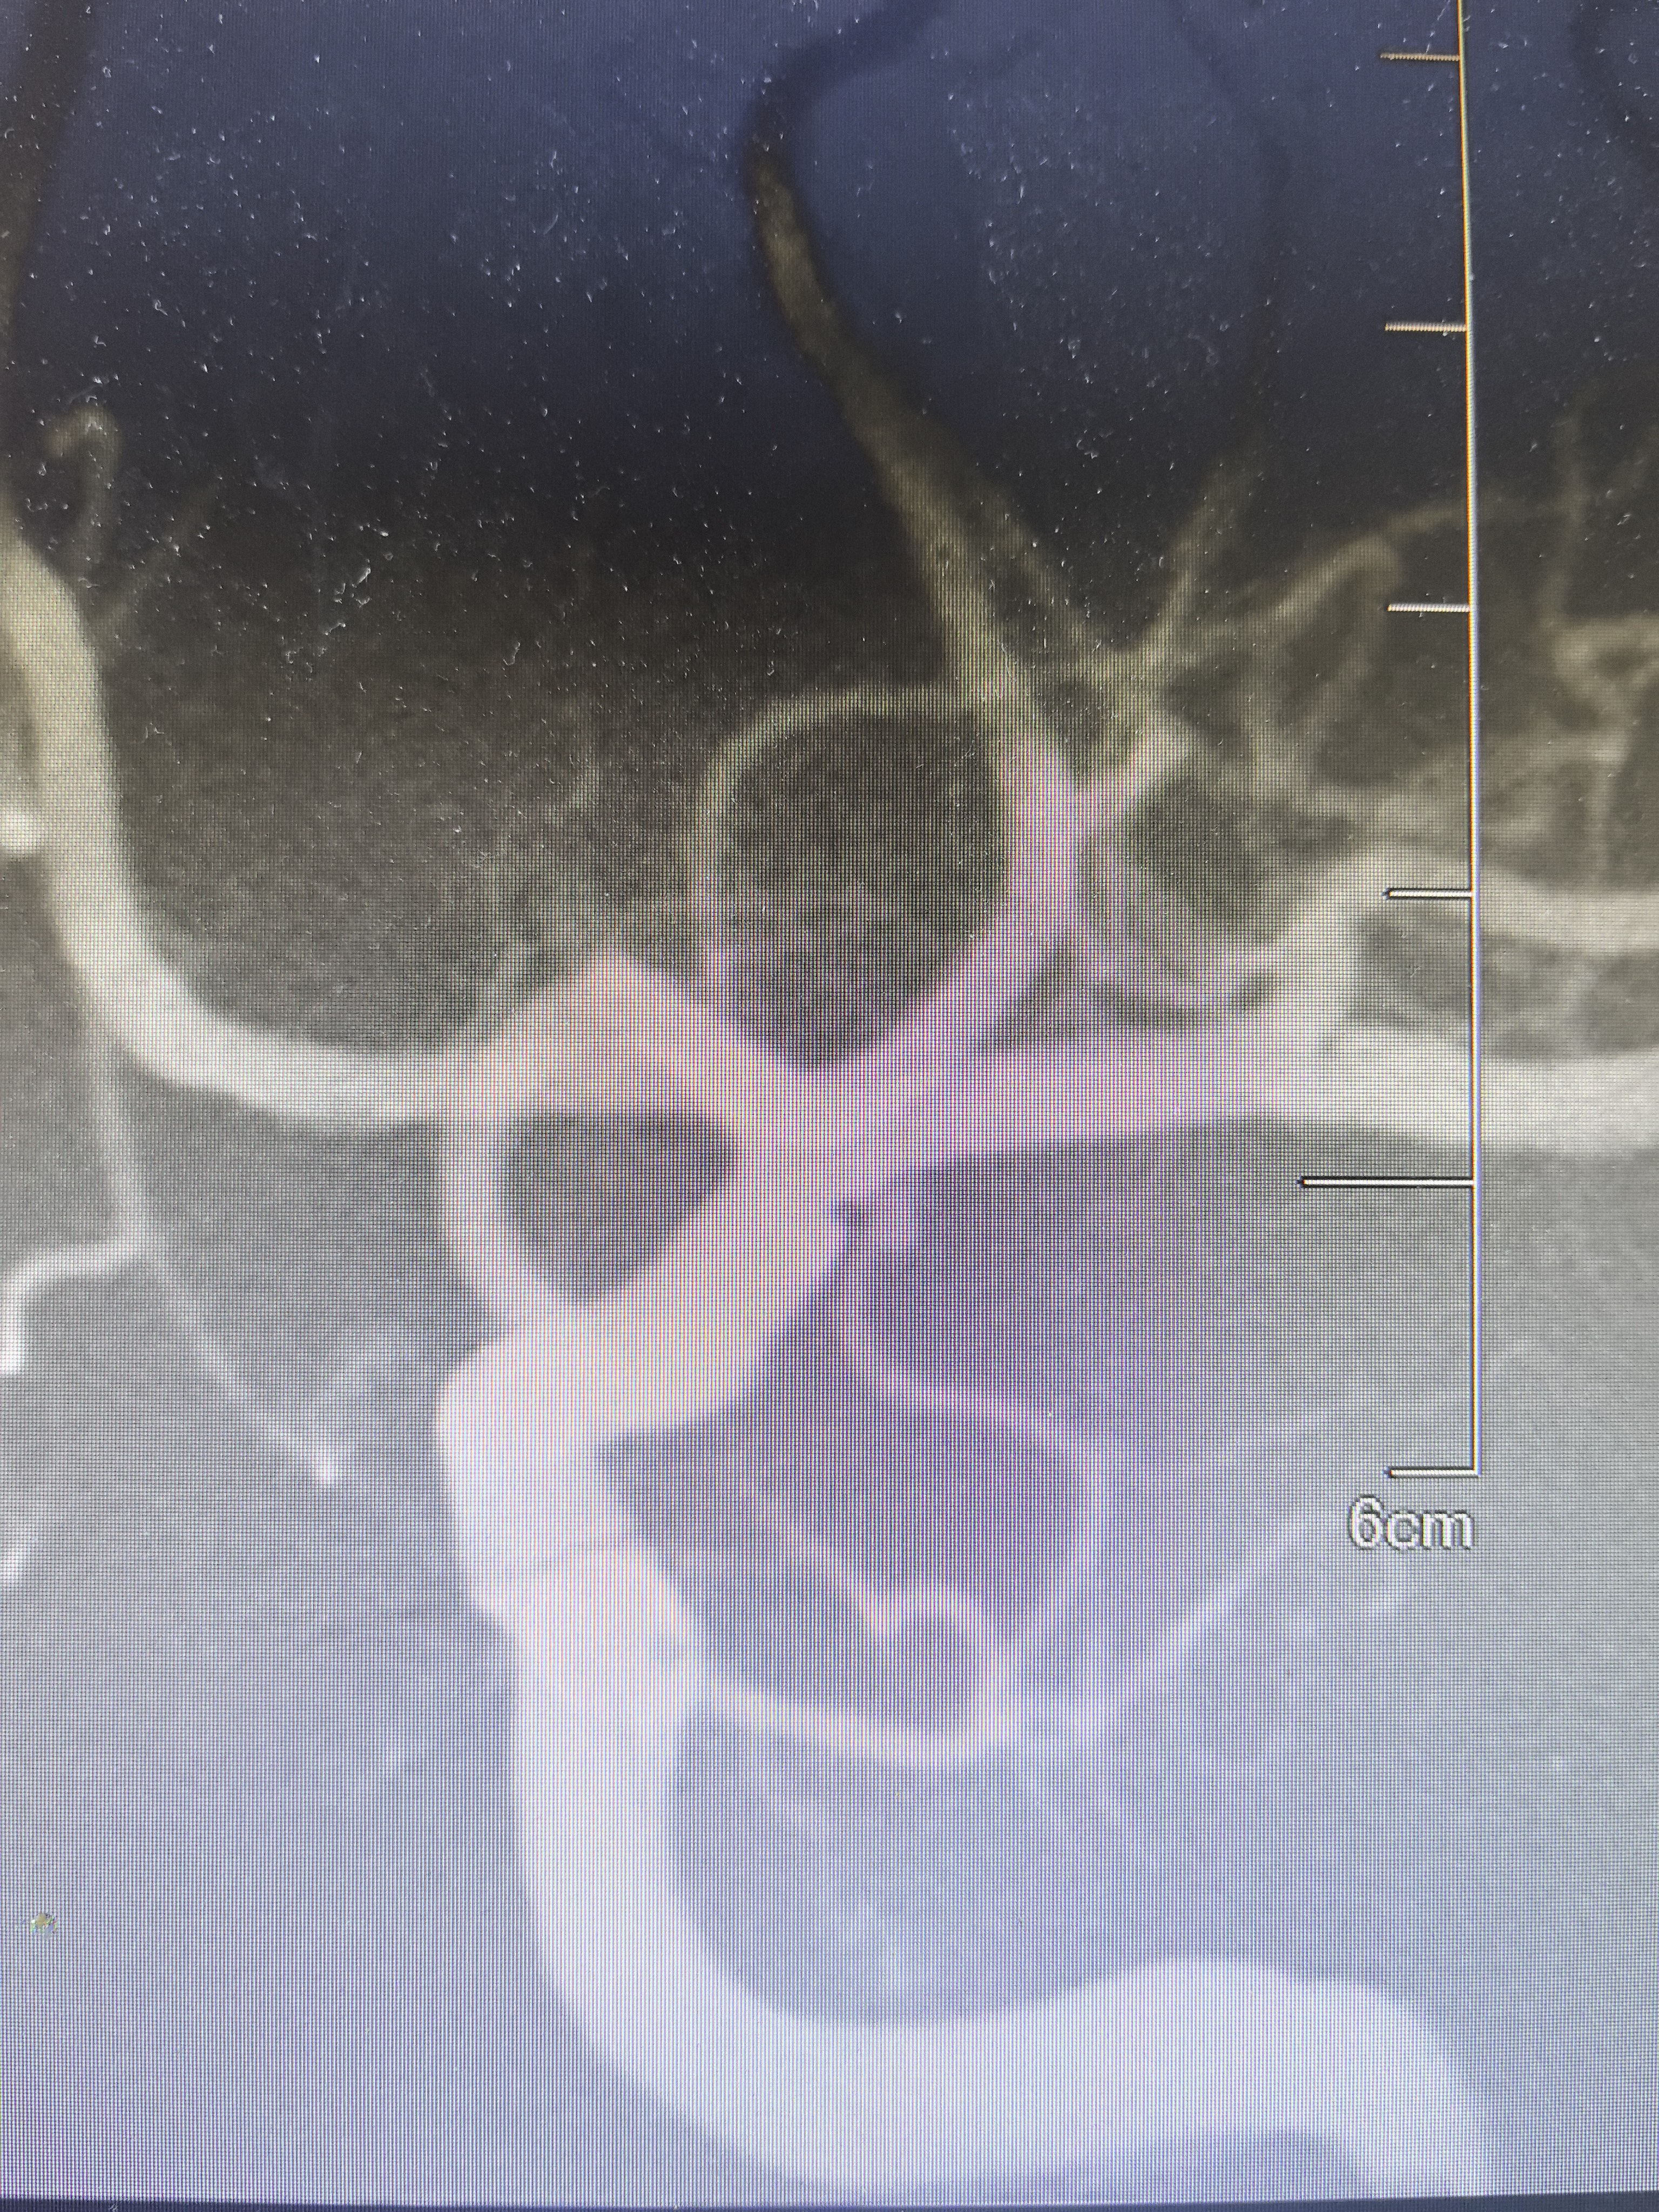

DSA显示左侧变异颞前早期分支起始部微小动脉瘤

路途下显示动脉瘤